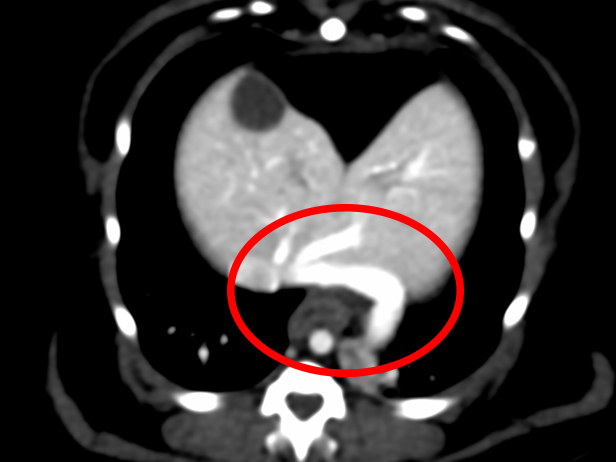

手術前のCT検査での評価(赤丸がシャント血管)